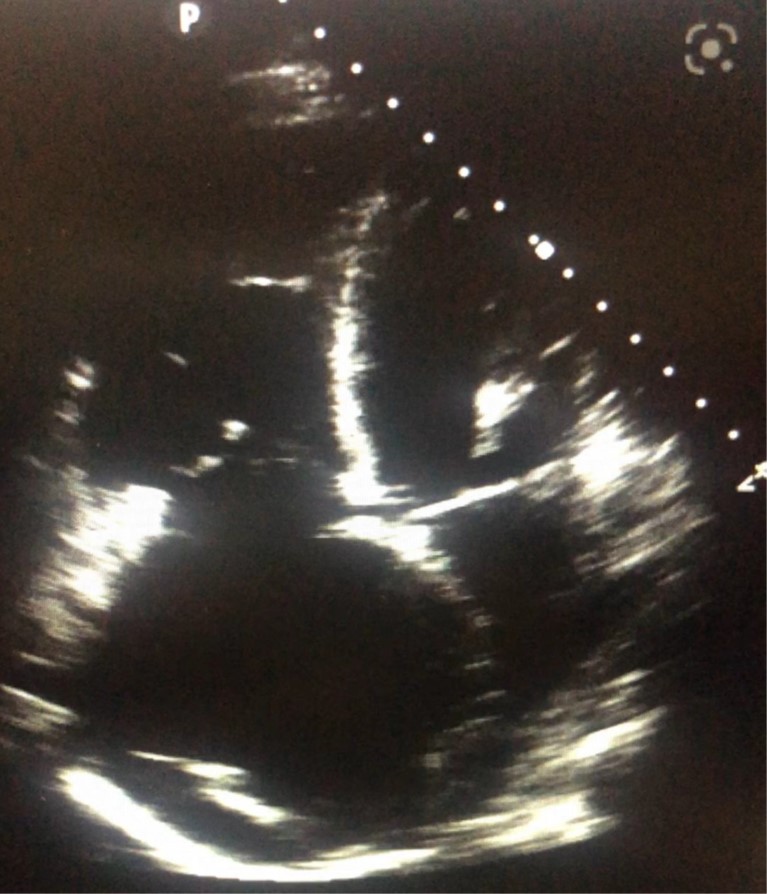

Trans esophageal echocardiography (TEE) was performed for her and revealed normal Left ventricle (LV) size and mild LV systolic dysfunction (LV ejection fraction of 50%). The right ventricular assessment showed severe right ventricle (RV) enlargement and sever RV systolic dysfunction. LV was D shaped during systole and diastole, too. there was severe akinesia of base and mid of RV free wall with sparing of RV apex (McConnell sign), in favor of massive PTE. MPA, LPA, and RPA were dilated containing a large mobile echogenic mass in PA bifurcation extending to LPA and RPA. Also, the posterior wall of left atrium (LA) was thickened that metastasis could not be ruled out. Intra-atrial septum (IAS) was redundant and aneurysmal with large size (5mm) permanent foramen oval (PFO) with bidirectional shunt (Figure 2).

Figure 2. TTE revealed severe RA (a) and RV (b) enlargement and McConnell sign.